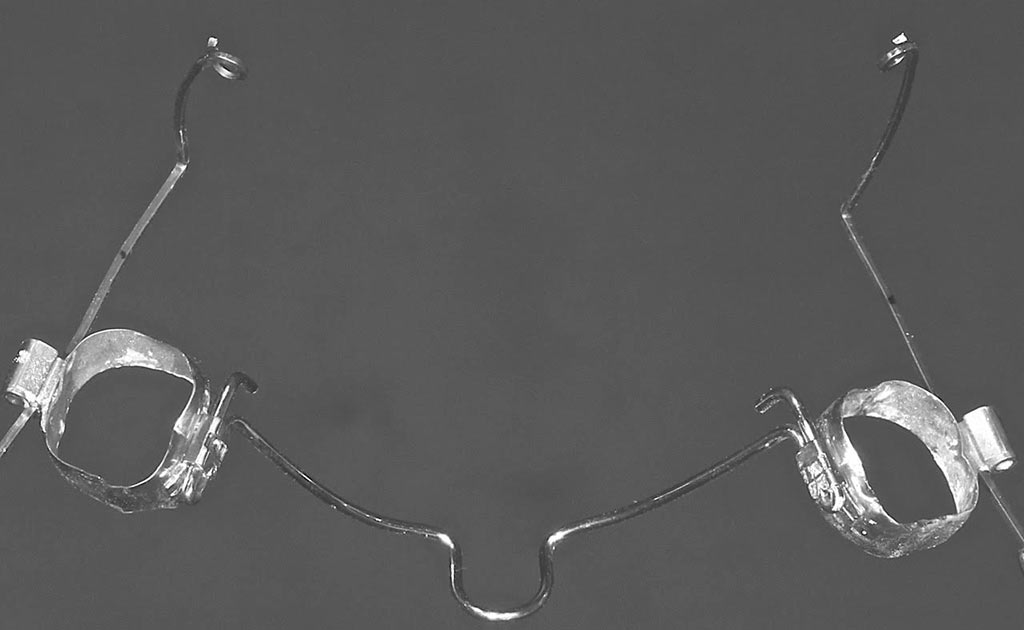

Tracción de canino con k9